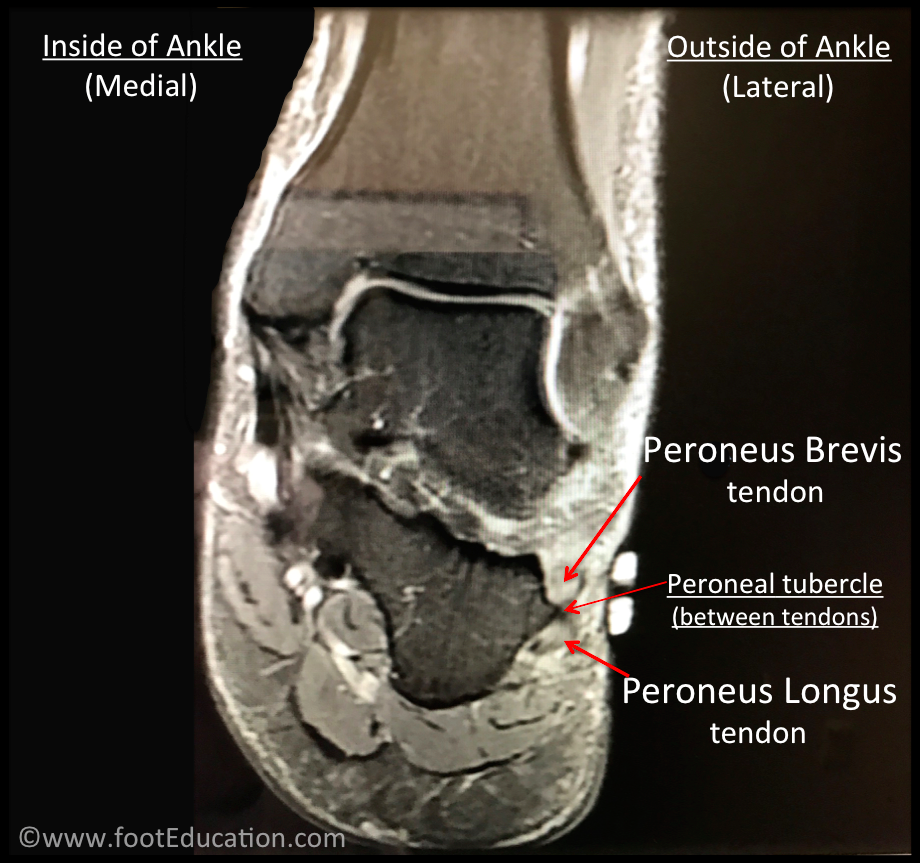

Anatomy Of The Peroneus Brevis Muscle —. Grundsätzlich werden die Sehnen wiederholt überlastet und die darauf folgende Entzündungsreaktion (Versuch einer Heilung) verursacht die Schmerzen und Unannehmlichkeiten. Die Sehnenscheide ermöglicht das reibungslose Gleiten der Sehne, doch bei einer Überlastung oder falschen Belastung kann die Sehnenscheide gereizt und entzündet werden.

Peroneus longus, brevis & tertius Schmerzen, Triggerpunkte und deren Aktivierung YouTube. Bei einer Entzündung der Peronealsehne können verschiedenste Übungen genutzt werden, um gegen die Schmerzen an der Peroneussehne und die Bewegungsbeeinträchtigungen anzugehen. Diese Sehnen spielen eine wichtige Rolle bei der Stabilität und Bewegung des Fußes.